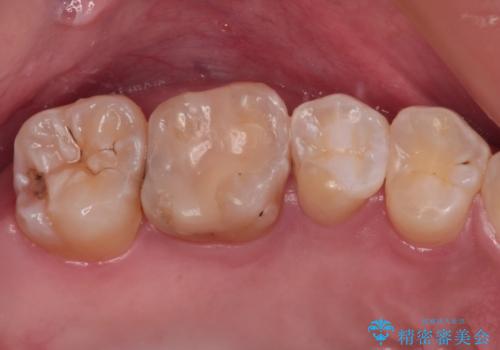

- 奥歯が割れてしまい、抜歯が必要となった患者様です。

以前にも歯が割れてインプラント治療を行いましたが、抜歯してからインプラント埋入→仮歯装着までに半年以上を要し、その間に残された歯への負担が大きくなり、セラミッククラウンが破折したことがありました。

そのため、当院に新しく導入した手法により、抜歯をした日にインプラントを埋入し、そのままを仮歯を装着することで、他の歯への負担を軽減する計画を立てました。